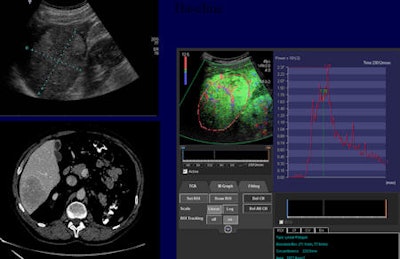

A major source of disagreement, however, is timing discordance in the AP, as shown in a patient with primary colon cancer with a suspicious mass in the liver, she noted. With CEUS, four seconds following completion of AP flush, the mass was clearly hypervascular, whereas at 10 seconds, the lesion is already washing out, and at 18 seconds the liver is enhanced and the lesion has completely washed out. On CT, both in the AP and PVP, this lesion is "just" a low attenuation mass lesion.

"If we plot the enhancement of the liver and the metastasis, we can see that the metastatic lesion enhances very rapidly, and by the time the liver enhancement has come up almost to its peak, the metastasis drops below it," Wilson explained. "If we consider that the CT AP images were taken in this time frame, it is no surprise that we miss that transient hypervascularity, which occurs in virtually all lesions. This timing discordance is something we anticipate seeing in patients with liver metastatic disease."